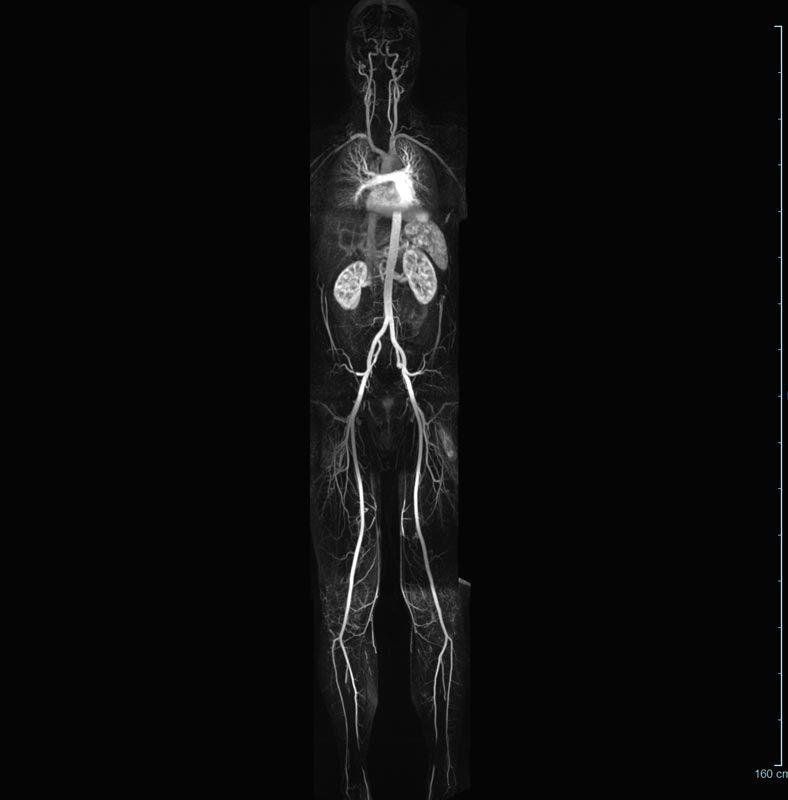

MR-Angiografie (MRA)

Angiographie ohne Kontrastmittel

• MR-Angiografie ohne Kontrastmittel

• Time of Flight (TOF)-Angiographie

• Phasenkontrastangiographie (PCA). Geeignet zur Quantifizierung Stenose-/Insuffizienzgrad z.B. bei Herzklappen, falls echokardiographisch die Untersuchungsbedingungen eingeschränkt sind.

Je nach Fragestellung und Körperregion Gefäßdarstellung ohne Kontrastmittel bei Kontrastmittelunverträglichkeit oder terminaler Niereninsuffizienz möglich.

Ganzkörper Angiographie mit Kontrastmittel

• MR-Angiographie mit Kontrastmittel

• Erfassung arterieller und venöser Gefäße/Bypässe aller Körperregionen mit 3D-Rekonstruktion

• je nach klinischer Fragestellung zeitaufgelöste MR-Angiographie (4D-MRA) z.B. bei Frage arteriovenöse Fistel/ Shunt oder Darstellung Unterschenkelarterien vor geplanter Bypassoperation.